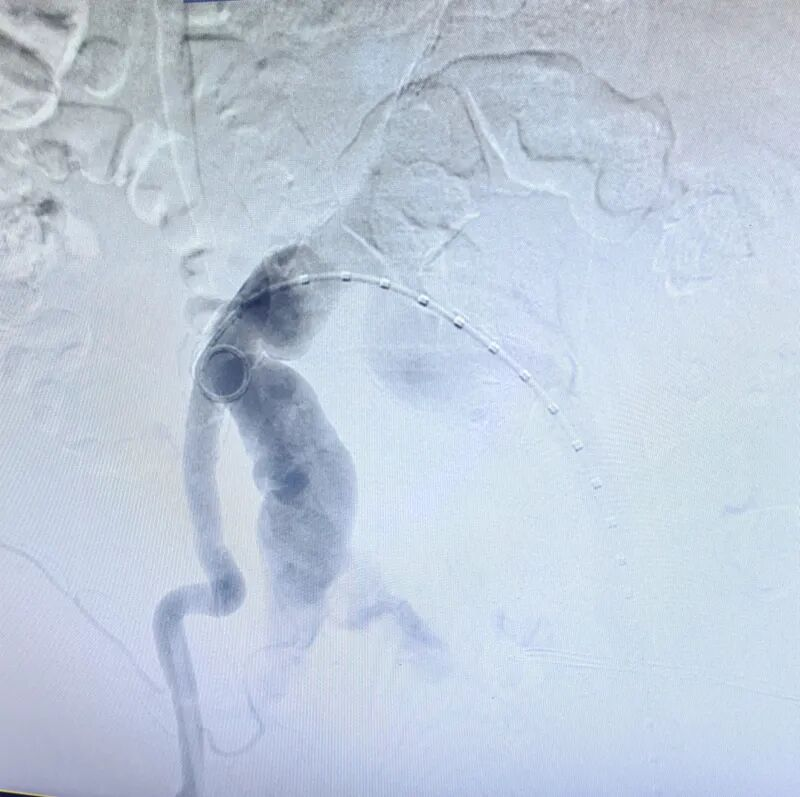

▲造影提示右侧髂内动脉瘤破裂,活动性出血